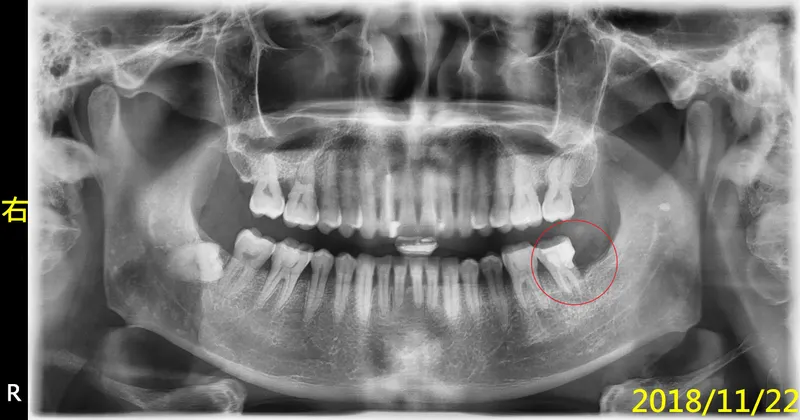

說明『根管治療後,不做牙套,是多麼的危險,會導致前功盡棄(保留牙齒廢物利用,不要拔牙)』,何況他還要先做『牙冠增長術』....所以,為了幫智齒擦屁股、收拾爛攤子,您看事後要付出多大的代價....他後來當然就自動消失啦,去找願意幫他便宜處理的所謂良心牙醫啦,只不過,撐不到一年,他就又回來找我啦....